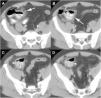

The presence of an MD in a MDCT should be suspected when a blind tubular structure connected to the terminal ileum by a neck of variable size is observed. Multiplanar 2D reconstructions images and CT enterography can help in the diagnosis. In patients with symptoms of obstruction or intestinal inflammation, the possibility of a complication secondary to a MD should be considered, especially when the terminal ileum and the vermiform appendix are normal. MDCT angiography, in cases of acute gastrointestinal bleeding, can identify contrast extravasation and accumulation of blood in the MD, and could demonstrate the persistent omphalomesenteric artery, which is diagnostic of MD. Other MDCT findings such as the presence of enteroliths or associated inflammatory changes around the MD can facilitate the preoperative diagnosis of MD complications.